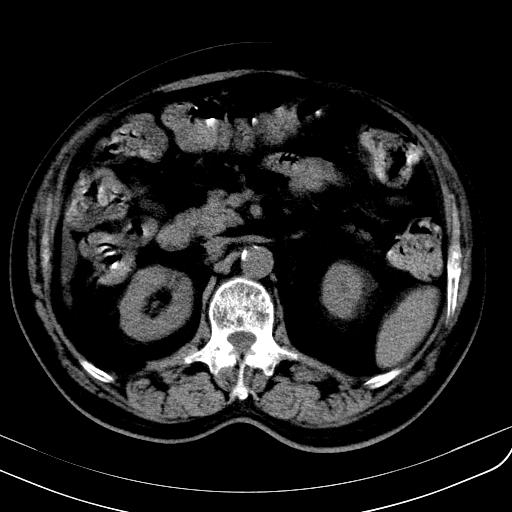

胃底靠近胃大弯处可见一圆形软组织影,直径为3.45cm,ct值约为30.1hu